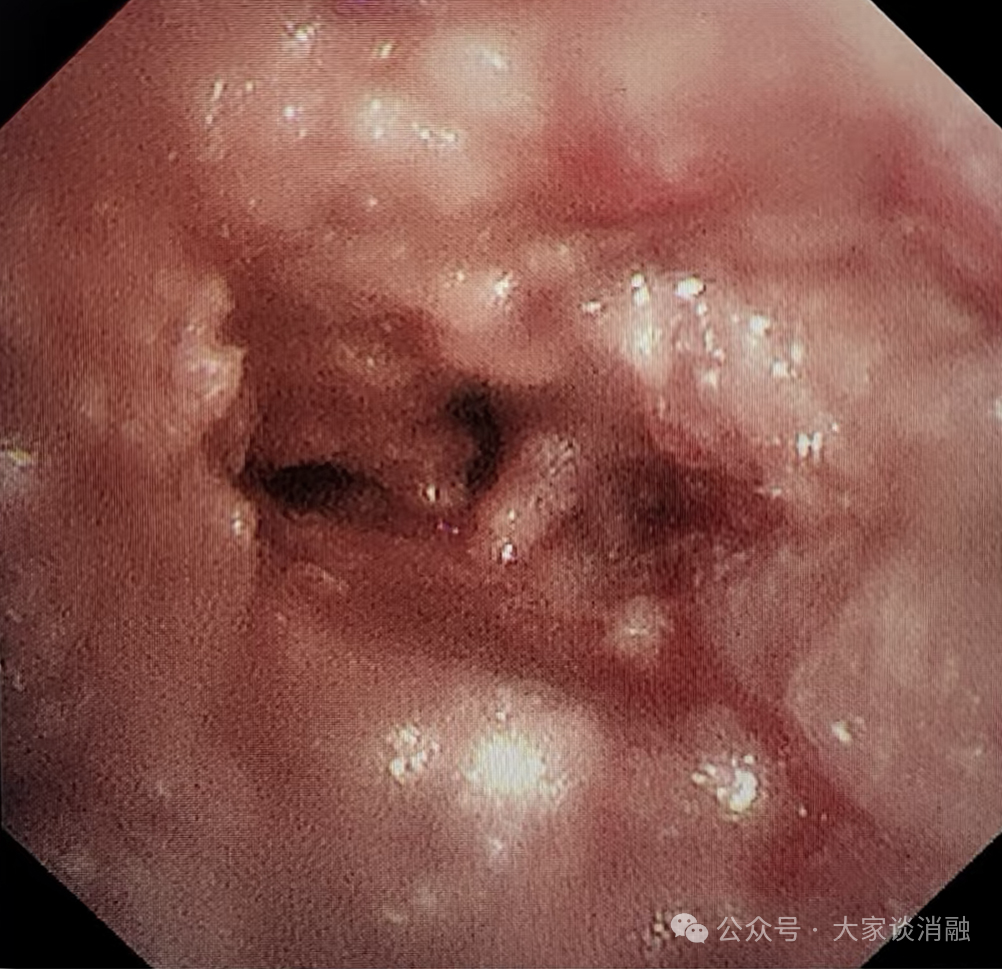

第三次治疗

10 月 29 日,为进一步巩固疗效,患者接受术后第二次镜下消瘤治疗,冷冻冻取、钳取肿瘤组织,气道阻塞问题得到更有效解决,生活质量显著提升。目前,患者已顺利出院,回归正常生活。

下叶完全开通